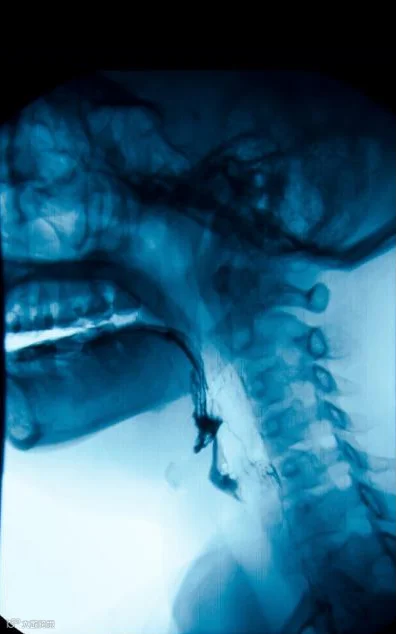

林阿姨,83岁,既往高血压、脑梗死病史。平时进食、饮水速度稍快,就会出现呛咳,但未重视。后来进食呛咳情况越来越明显,并反复因为发热,咳嗽,多次住院治疗。那像林阿姨这种病人,为什么会经常出现呛咳呢?该如何预防呢?

吞咽障碍

【什么是吞咽障碍】

【吞咽障碍的原因】

老年人:食管上括约肌老化,舌肌力量的下降、吞咽反射触发延迟,喉延迟闭合、残留率和渗透率增加,引起吞咽后食物残留,肌肉组织和功能的减少、组织弹性变化、唾液生成减少及口腔牙齿等变化,这些都增加了老年人吞咽困难的易感性。